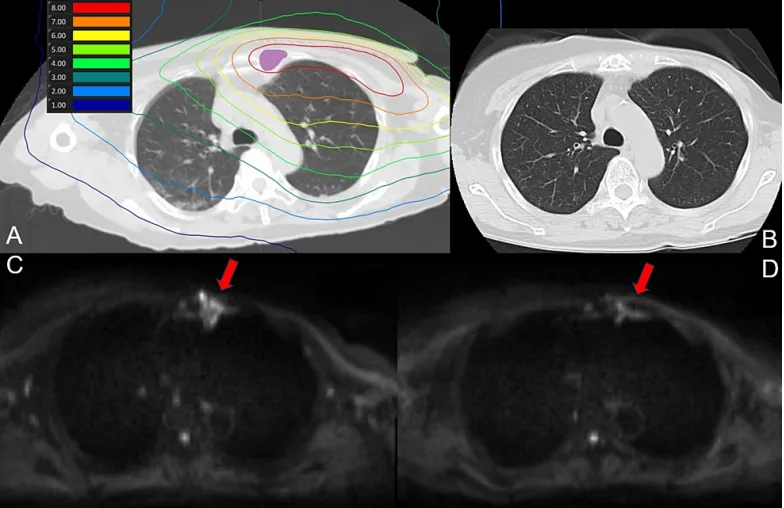

該患者在BNCT治療前有12年以上的左側(cè)乳腺癌化療史,隨后進(jìn)行了乳房切除,后左側(cè)胸骨旁淋巴結(jié)復(fù)發(fā),接受了激素治療和化療。4年前,該患者接受了左側(cè)胸壁和胸骨旁區(qū)域的放射治療,共30次,總劑量為59Gy,盡管此區(qū)域治療后未再復(fù)發(fā),但左側(cè)乳腺內(nèi)淋巴結(jié)出現(xiàn)復(fù)發(fā),遂開始BNCT治療。腫瘤靶區(qū)(GTV) 的最小處方劑量為31.4Gy-Eq,同側(cè)肺的平均劑量為5Gy-Eq。在BNCT治療后第1和第7天對(duì)患者進(jìn)行了MRI檢查,第30和90天進(jìn)行了CT檢查,均未發(fā)現(xiàn)放射性肺炎跡象。圖1顯示了肺部區(qū)域的劑量分布以及治療后90天的CT和MRI掃描結(jié)果。

圖1

(A) BNCT(肺)劑量分布圖。紫色代表腫瘤總體積

(B) 治療90天后CT掃描未見放射性肺炎征象

(C) 治療前彌散加權(quán)成像MRI

(D) MRI掃描90天顯示信號(hào)強(qiáng)度降低